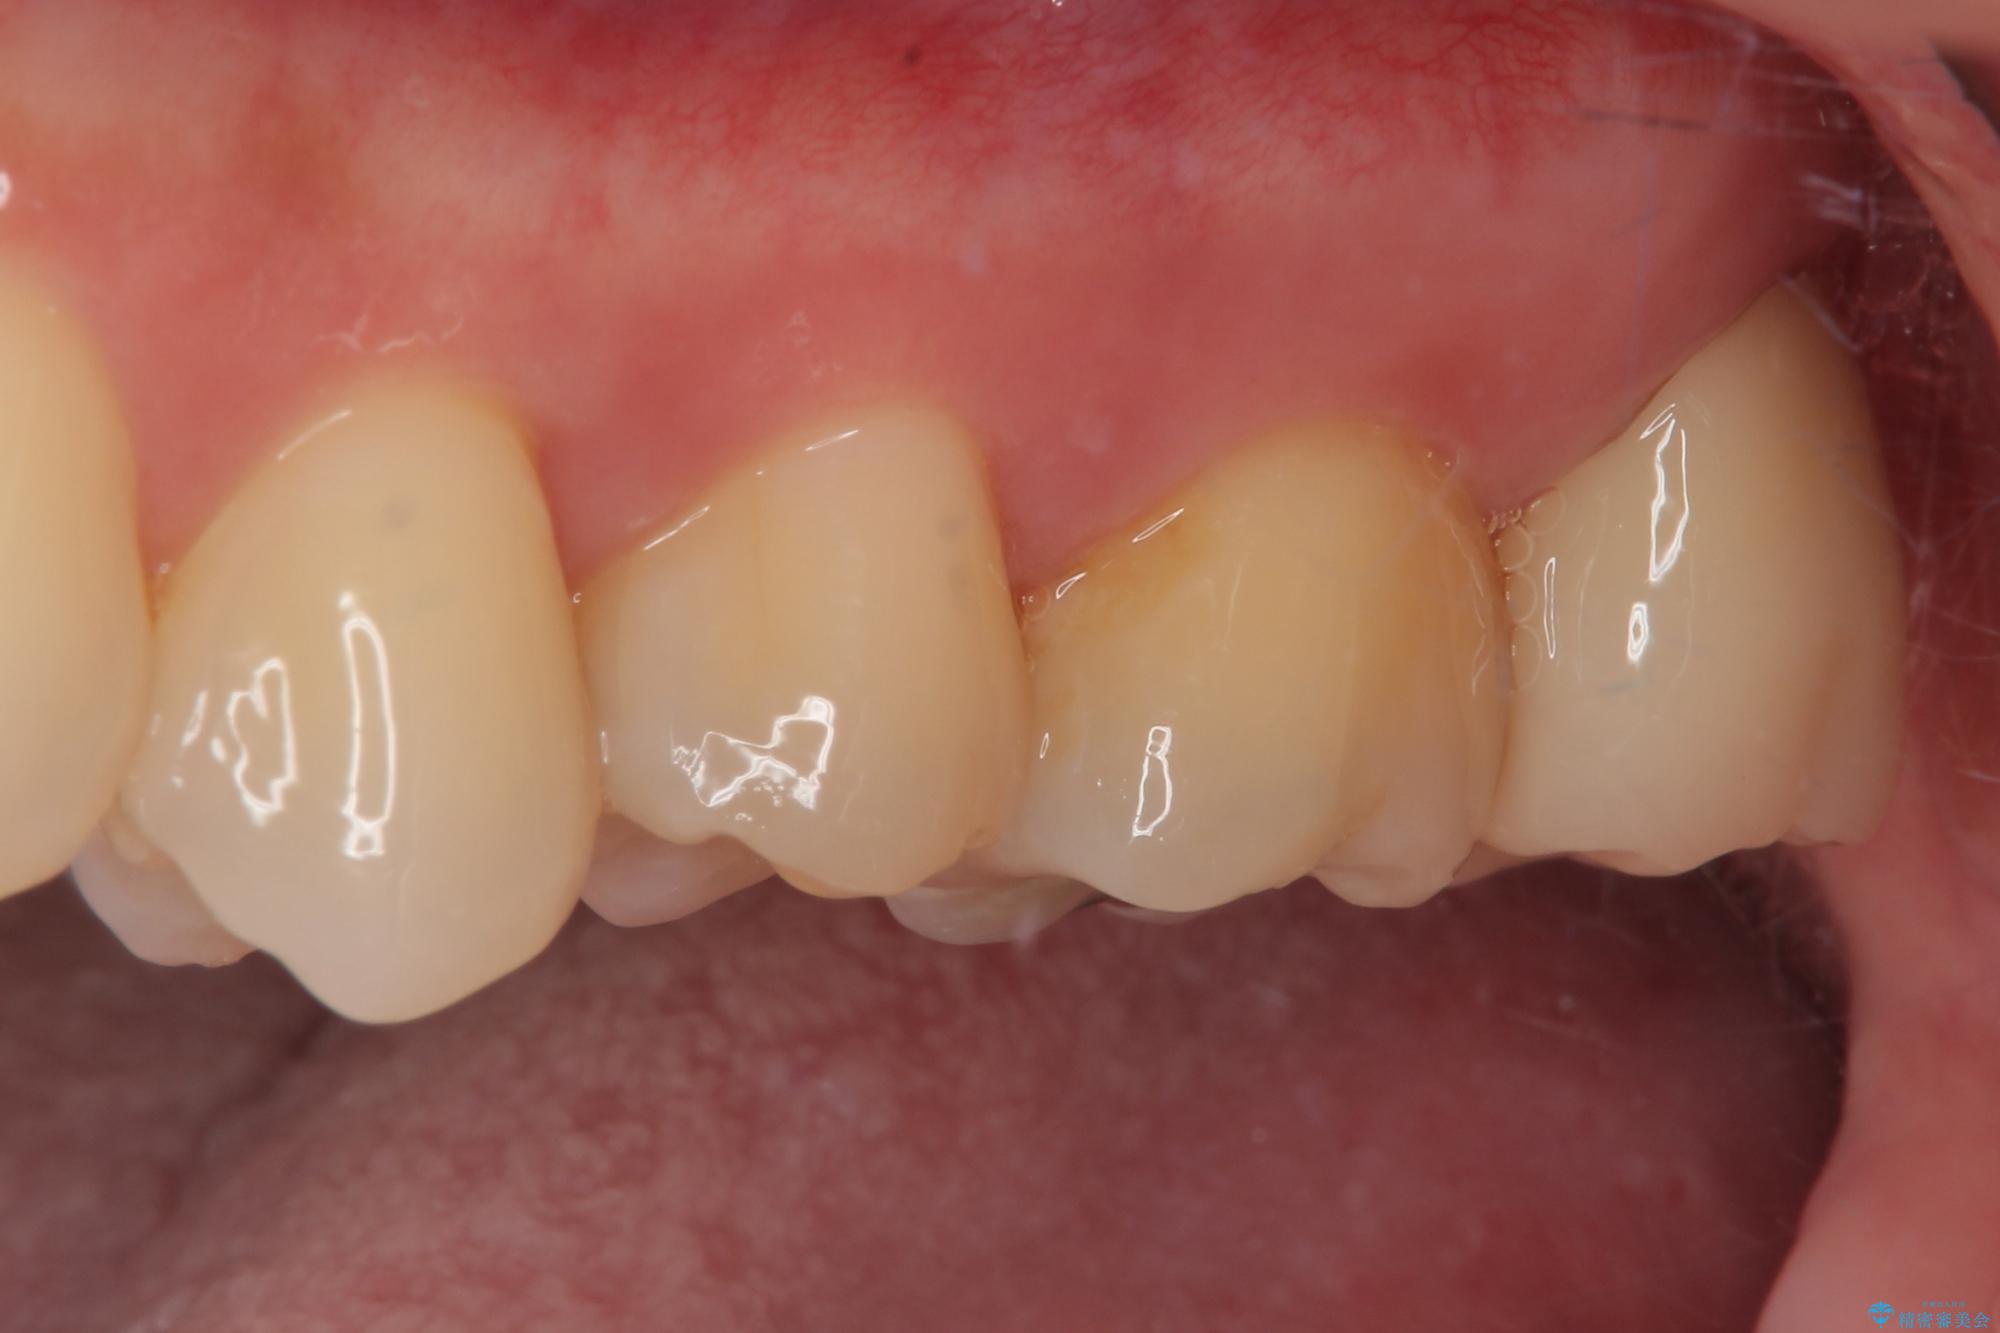

矯正治療により処置が可能な位置に歯が移動したため、オールセラミッククラウンにて補綴治療を行うこととしました。

歯列が移動したとはいえ、左右ともに後方傾斜しており、むし歯の除去、形成(形を整える)、型取りの全てが非常に困難な処置となりました。

セラミッククラウンの適合はレントゲン写真からも分かる通り、境界がぴったりと合った、高適合のものとなりました。